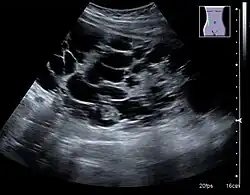

Complex cysts can have membranes dividing the fluid-filled center with internal echoes, calcifications or irregular thickened walls. The complex cyst can be further evaluated with Doppler US, and for Bosniak classification and follow-up of complex cysts, either contrast-enhanced ultrasound (CEUS) or contrast CT is used (Figure 6). The Bosniak classification is divided into four groups going from I, corresponding to a simple cyst, to IV, corresponding to a cyst with solid parts and an 85–100% risk of malignancy.[1] In polycystic kidney disease, multiple cysts of varying size in close contact with each other are seen filling virtually the entire renal region. In advanced stages of this disease, the kidneys are enlarged with a lack of corticomedullary differentiation (Figure 7).[1]

Figure 7. Advanced polycystic kidney disease with multiple cysts.[1]